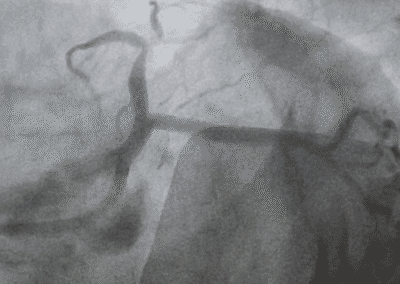

- Angioplastica: Un intervento minimamente invasivo per dilatare le arterie ristrette, ripristinando il flusso sanguigno.

- Bypass arterioso: Nei casi più gravi, un intervento chirurgico per creare una nuova via per il flusso sanguigno, bypassando le arterie ostruite.